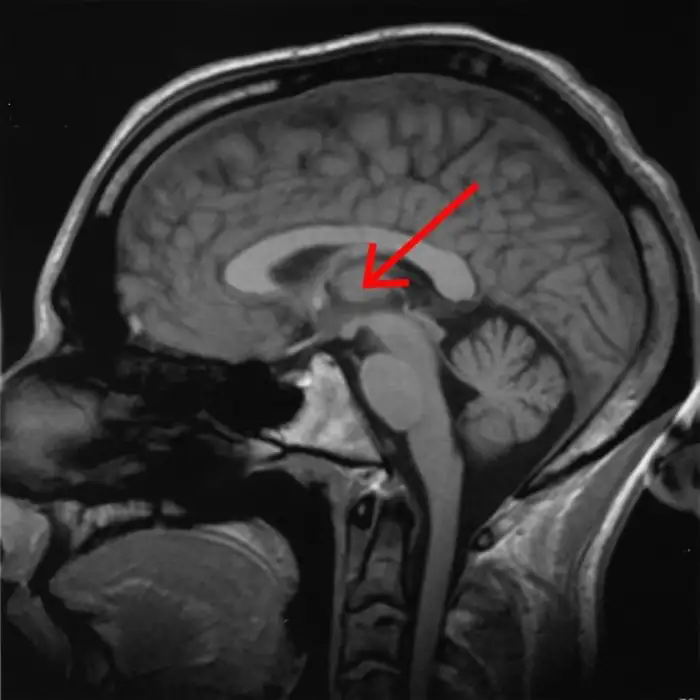

虽然意识的诞生过程,尚且停在假说

阶段,但研究人员极有可能已经找到了意识的开关——中央外侧丘脑。

6.jpg

(40.12 KB)

2025-2-10 14:59

威斯康星大学麦迪逊分校的研究人员发现,使用50 Hz电刺激中央外侧丘脑时,处于麻醉状态的猕猴能够苏醒,并出现正常的清醒行为。

猴子睁开眼睛,生命体征出现变化,面部和身体开始运动,并伸手去拿附近的物体。

不过,关闭电刺激之后,仅仅几秒钟,猴子便会再次闭上眼睛,回到无意识的状态。

上述实验,必须非常精准才能实现。

50 Hz的电脉冲,只能点击仅仅20纳米的特定位置。

这表明,中央外侧丘脑对意识具有一定的启动作用。

但这个实验,是否可以证明,意识也如同运动、感觉、视觉等中枢皮层有着明显的区域功能呢?

那倒是未必。